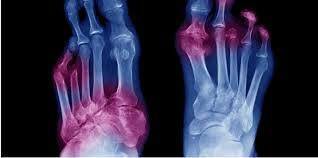

糖尿病足的特點是典型的三聯神經病變,缺血和感染。預防糖尿病足應是首要任務。這可以通過識別高危人群來實現,比如周圍神經病變、周圍血管疾病、足部畸形和骨痂。

Diabetic foot is characterized by a classical triad of neuropathy, ischemia, and infection.

Preventing the diabetic foot should be the first priority. This can be achieved by identifying the high-risk individuals, like those with peripheral neuropathy, peripheral vascular disease, foot deformities, and presence of callus.

Epidemiology: Diabetic foot ulcers are common and estimated to affect 15% of all diabetic individuals during their lifetime. It is now appreciated that 15 – 20% of patients with such foot ulcers go on to need an amputation. Almost 85% of the amputations are preceded by diabetic foot ulcers. Numerous risk factors for the development of foot ulcers have been suggested, the most important being peripheral sensory neuropathy followed by peripheral vascular disease. The proportion of neuropathic, neuroischemic, and purely ischemic lesions in diabetics is 54, 34, and 10%, respectively.[3] In India, it is estimated that approximately 40,000 legs are being amputated every year, of which 75% are neuropathic with secondary infection, which is potentially preventable. Certain factors, such as, barefoot walking, illiteracy, low socioeconomic status, late presentation by patients, ignorance about diabetic foot care among primary care physicians, and belief in the alternative systems of medicine contribute to this high prevalence.